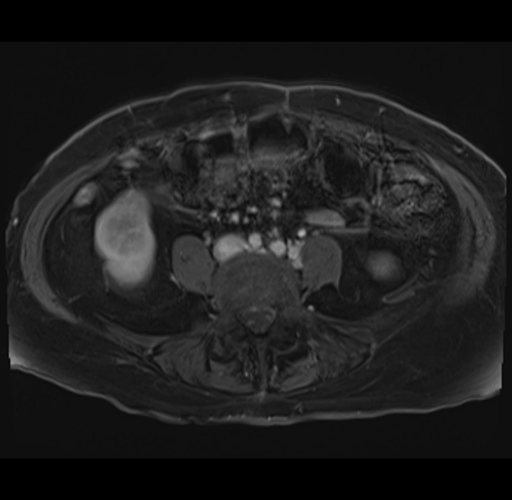

Imaging Analysis

Look through the patient's CT scan to identify any areas of concern for the necessary procedure.

MRI T1

Based on your CT findings, which issue(s) would give reason for "planned slowing down moment(s)" in this case?

Considering a standard right hepatectomy procedure, what step(s) of the operation would you do differently in this case?